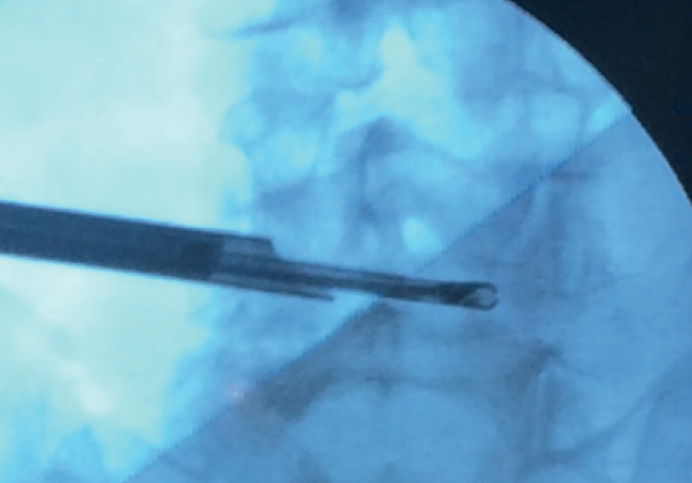

Figure 6. Radiological view of contralateral single-portal interlaminar endoscopy. Access through the contralateral interlaminar window and progress over-the-top to the contralateral recess, allowing the contralateral vertebral foramen to be reached and explored.